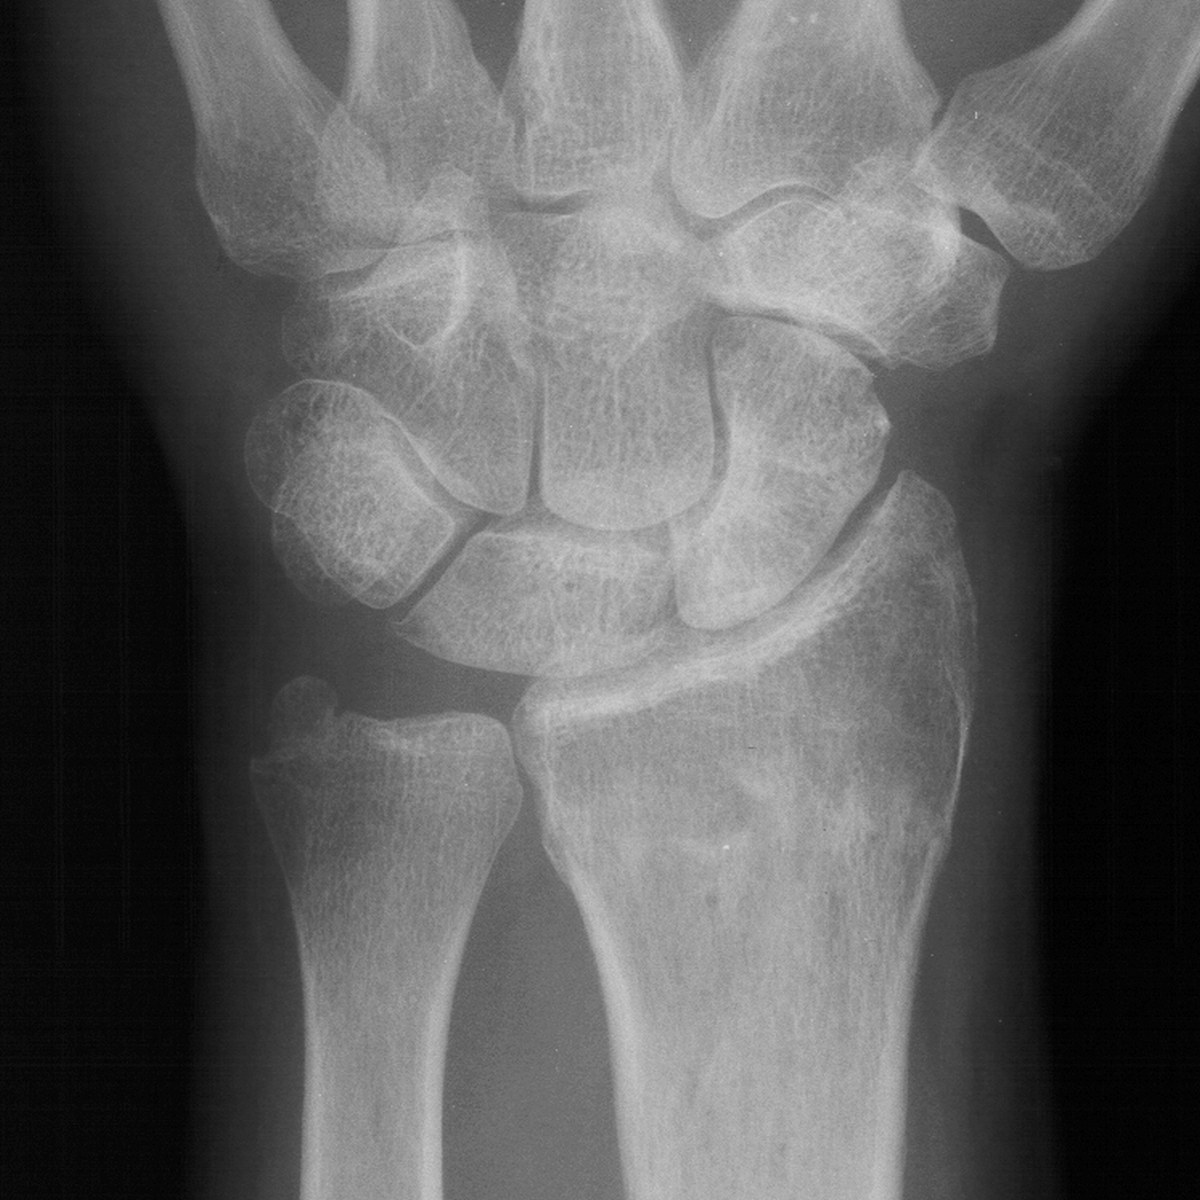

| Case 6 Extraarticular distal radius fracture with angulation and dorsal comminution. |

| Attempts at

closed reduction alone were unsuccessful. |

| Freer elevator

introduced percutaneously as a reduction aid. |

| Percutaneous

fracture stabilization with three pins via the

dorsal radial tubercle, radial styloid and FCR

portals. |

| Pins were left

protruding and bent to overlap. |

| Thermoplastic-pin

construct at 6 weeks, immediately prior to removal. |

| Late result. |